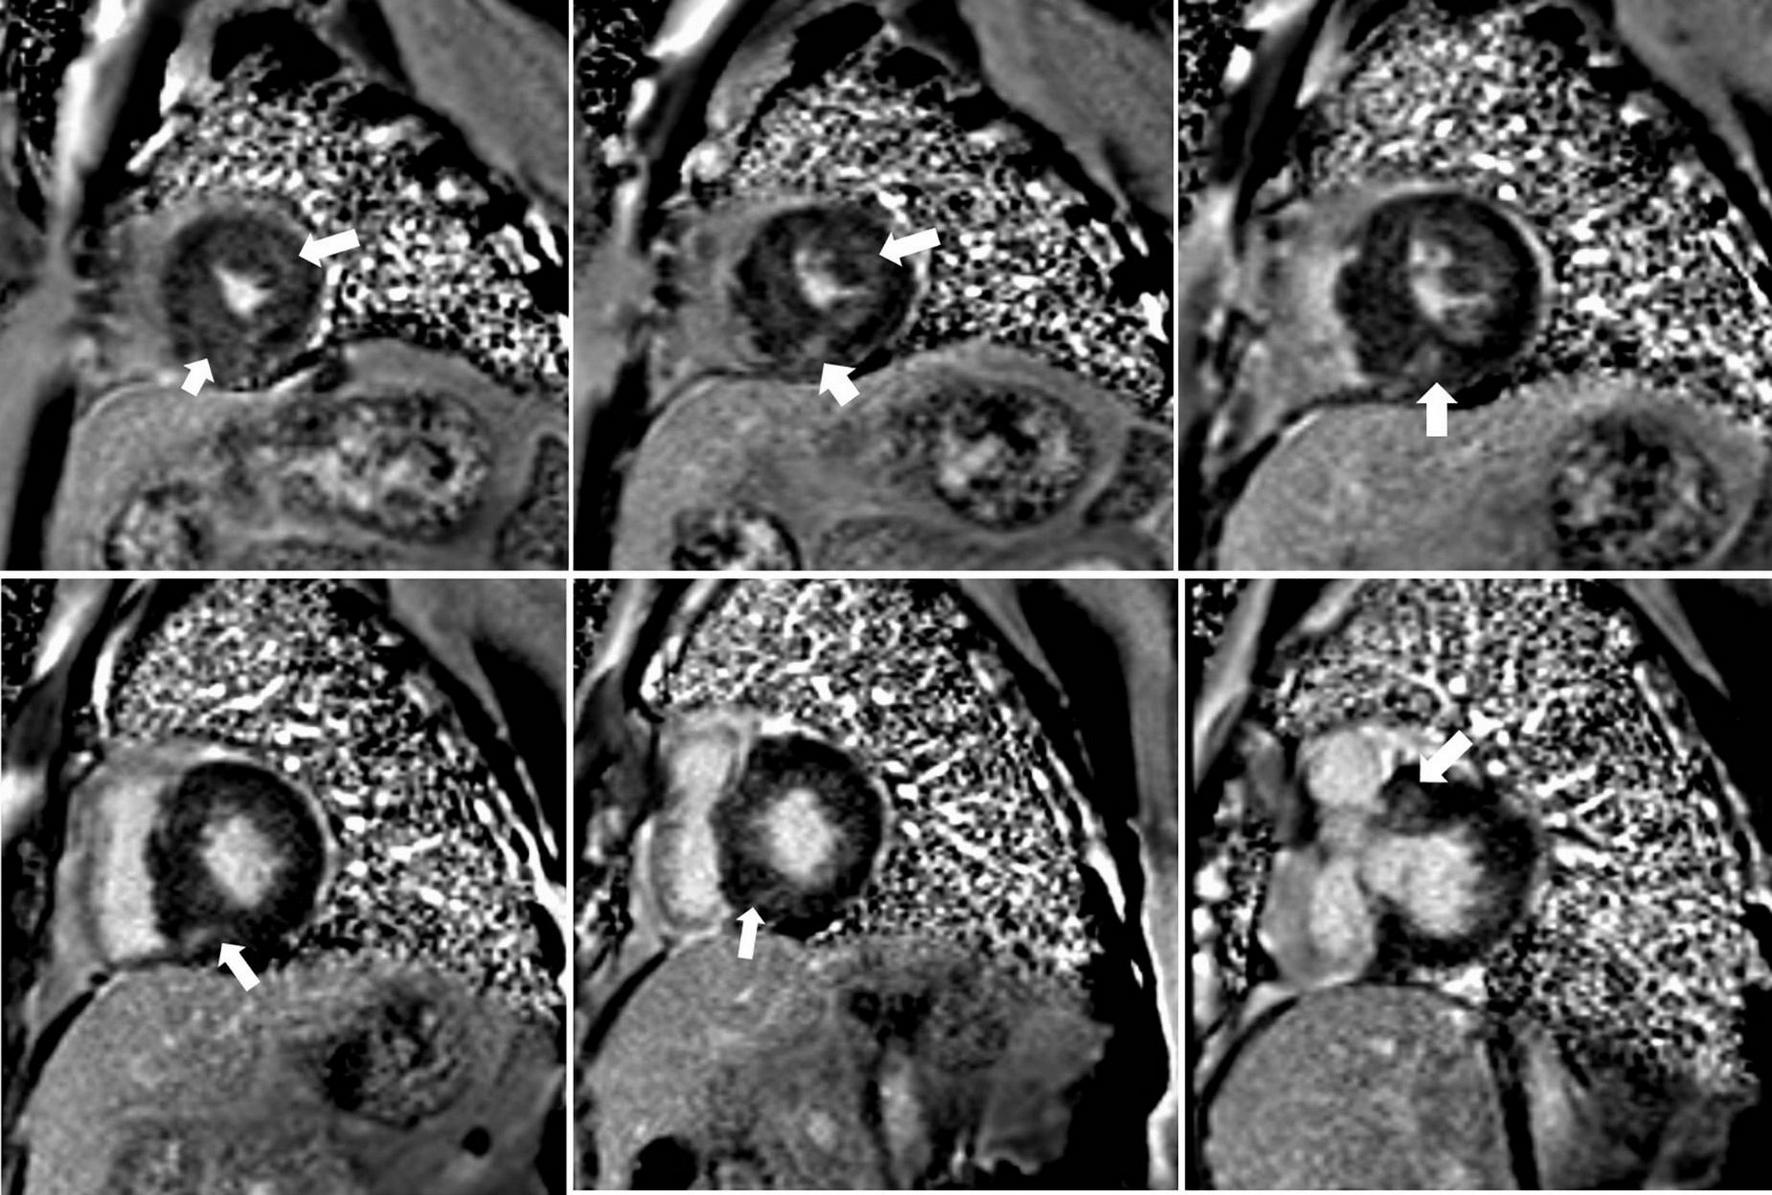

FIGURE 1

Representative short-axis late gadolinium enhancement (LGE) images in a 35-year-old male with obstructive hypertrophic cardiomyopathy showing diffuse hyperenhancement (white arrows) in the ventricular septum with 11.3% LGE compared to the LV mass.